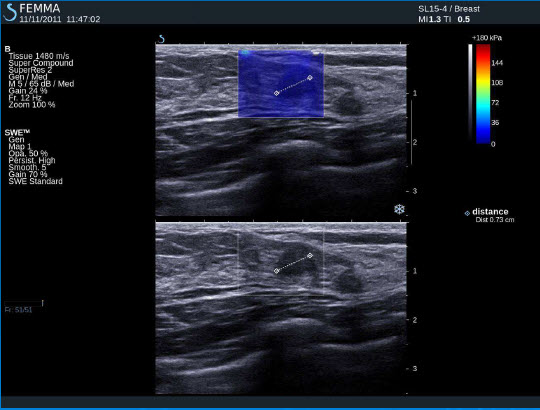

Fibroadenom